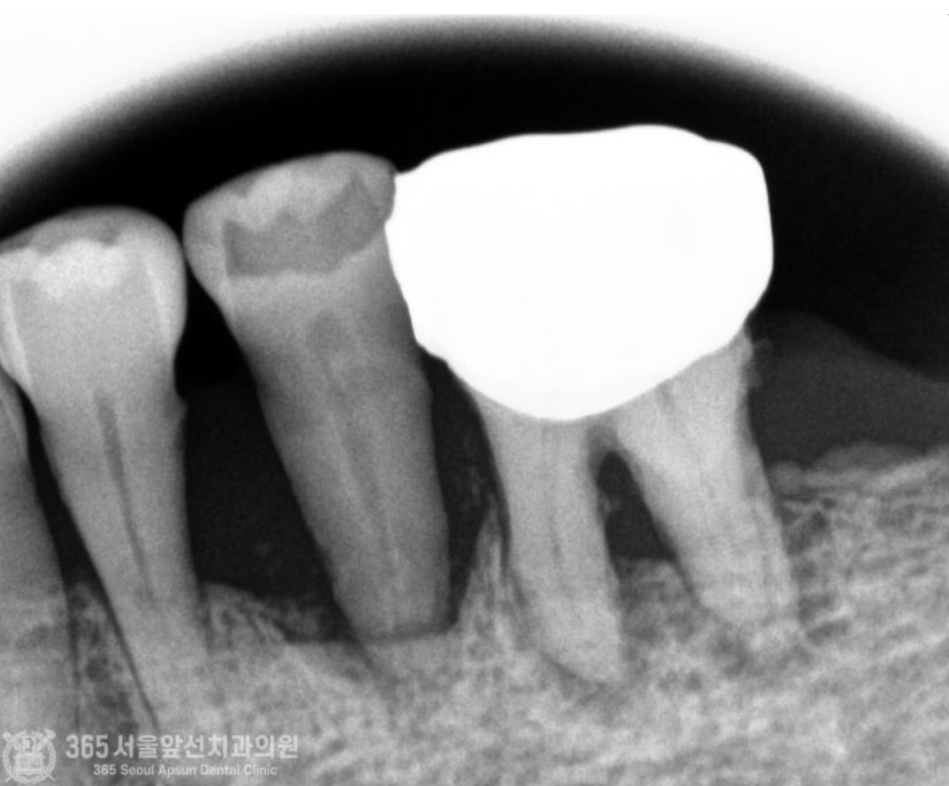

촬영일시 : 24.06.12 정밀한 검사를 위해 작은 엑스레이 사진도 촬영했습니다. 치아 뿌리 끝까지 뼈 손실이 발생되어 매우 심각한 상태임을 알 수 있습니다.